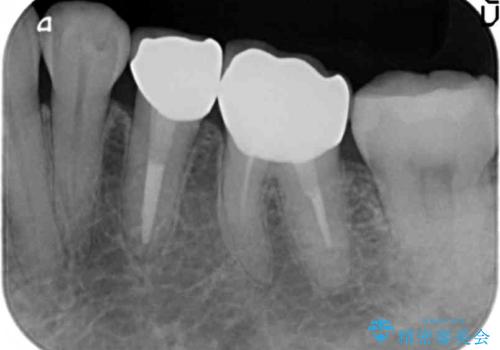

下の銀歯をセラミックに 虫歯治療

- 左下の銀歯を白くしたいと来院。

左下5番は根管治療のやりなおし、左下6番は上物(クラウン)のやり替えのみを行いました。

左下7番はアマルガムが入っていたため、ご希望によりセラミックインレーで治療を行っています。

- 44万円(内訳 左下7:emaxプレスインレー 左下6:仮歯、ジルコニアクラウン 左下5:精密根管治療再治療、ファイバーコア、仮歯、ジルコニアクラウン)費用は治療当時の料金となります